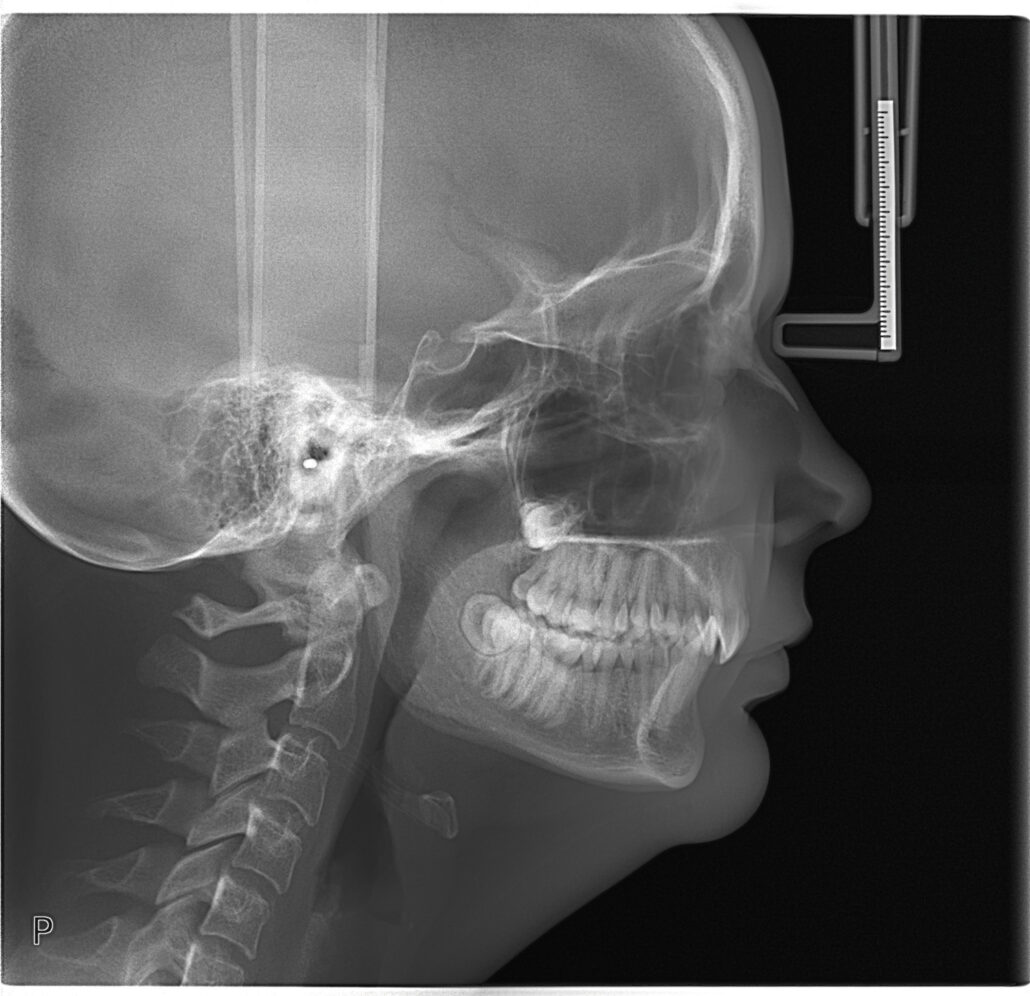

CEPH X-Ray

A cephalometric x-ray is a unique tool, which enables the dentist to capture a complete radiographic image of the side of the face. X-rays, in general, offer the dentist a way to view the teeth, jawbone and soft tissues beyond what can be seen with the naked eye. Cephalometric X-rays are extraoral, meaning that no plates or film are inserted into the mouth. Cephalometric and panoramic X-rays display the nasal and sinus passages, which are missed by intraoral bitewing X-rays.

Cephalometric X-rays are usually taken with a panoramic X-ray machine. The adapted machine will have a special cephalometric film holder mounted on a mechanical arm. An X-ray image receptor is exposed to ionizing radiation in order to provide the dentist with pictures of the entire oral structure. The advantage of both cephalometric and panoramic X-rays is that the body is exposed to less radiation.

- Provide views of the side profile of the face.

- Provide views of the jaw in relation to the cheekbone.

- Allow measurement of the teeth.

- Assists in orthodontic planning.

Cephalometric X-rays are completely painless. The head is placed between the mechanical rotating arm and the film holder, which is placed on another arm. The arm rotates around the head capturing images of the face, mouth and teeth. The clarity and sharpness of these images will depend on the positioning of the body. The images are usually magnified up to 30%, so any signs of decay, disease or injury can be seen and treated.

After capturing cephalometric X-rays, the dentist will be able to see a complete side profile of the head. This can assist in orthodontic planning, and allow an immediate evaluation of how braces might impact the facial profile and teeth. Another common use for this type of X-ray is to determine specific measurements prior to the creation and placement of dental implants.